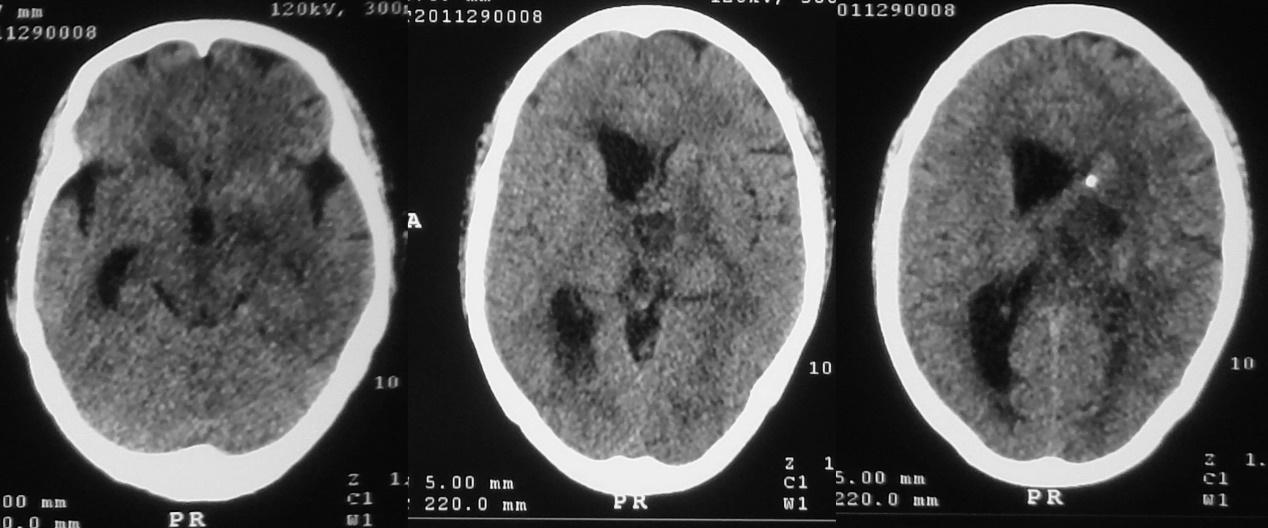

患者于2020年11月8日无明显诱因出现间断头痛。发病5天后,即2020年11月13日到当地的河南省潢川县某医院行头颅CT检查( 图-1 )发现左侧丘脑病变。

图-1: 2020年11月13日头CT